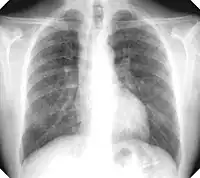

There are three key elements to the diagnosis of silicosis. First, the patient history should reveal exposure to sufficient silica dust to cause this illness. Second, chest imaging (usually chest x-ray) that reveals findings consistent with silicosis. Third, there are no underlying illnesses that are more likely to be causing the abnormalities. Physical examination is usually unremarkable unless there is complicated disease. Also, the examination findings are not specific for silicosis. Pulmonary function testing may reveal airflow limitation, restrictive defects, reduced diffusion capacity, mixed defects, or may be normal (especially without complicated disease). Most cases of silicosis do not require tissue biopsy for diagnosis, but this may be necessary in some cases, primarily to exclude other conditions. Assessment of alveolar crystal burden in bronchoalveolar lavage fluid may aid diagnosis.[19]

For uncomplicated silicosis, chest x-ray will confirm the presence of small (< 10 mm) nodules in the lungs, especially in the upper lung zones. Using the ILO classification system, these are of profusion 1/0 or greater and shape/size "p", "q", or "r". Lung zone involvement and profusion increases with disease progression. In advanced cases of silicosis, large opacity (> 1 cm) occurs from coalescence of small opacities, particularly in the upper lung zones. With retraction of the lung tissue, there is compensatory emphysema. Enlargement of the hilum is common with chronic and accelerated silicosis. In about 5–10% of cases, the nodes will calcify circumferentially, producing so-called "eggshell" calcification. This finding is not pathognomonic (diagnostic) of silicosis. In some cases, the pulmonary nodules may also become calcified.

Chest X-ray showing uncomplicated silicosis